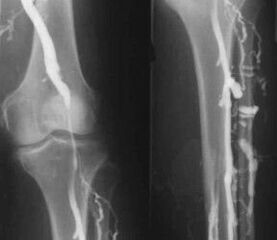

The most common instrumental diagnostic method is ultrasound examination of the venous vessels of the legs.This technique allows you to visualize the vascular system and see the progress of the pathological process.

- Phlebography.

- Photoplethysmography.

The use of venous occlusion plethysmography makes it possible to determine the blood volume in the veins of the lower extremities.